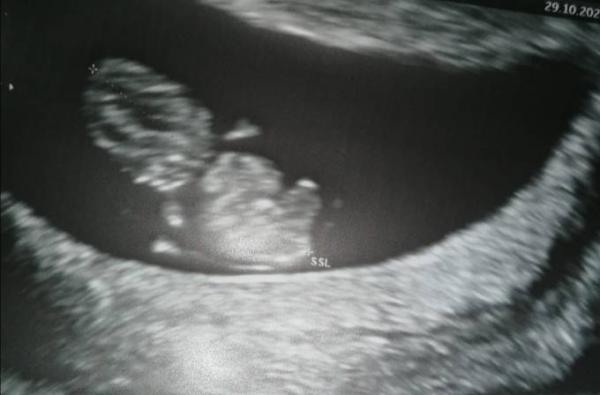

Hallo ihr Lieben, Ich hatte gestern bei 8+2 auch endlich meinen ersten ultraschall. Alles so wie es sein soll, Herzchen schlägt und das Würmchen war total aktiv ich bin wie beflügelt und Mega happy. Den Mutterpass habe ich gestern auch bekommen.

Bild zu Endlich erster Ultraschall 😍 - Forum für Juni - Mamis